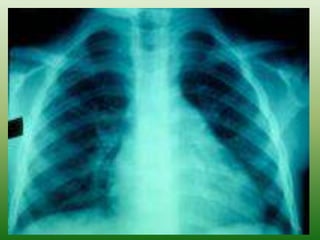

Diagnosis: Laboratory Studies (continued)

– CXR